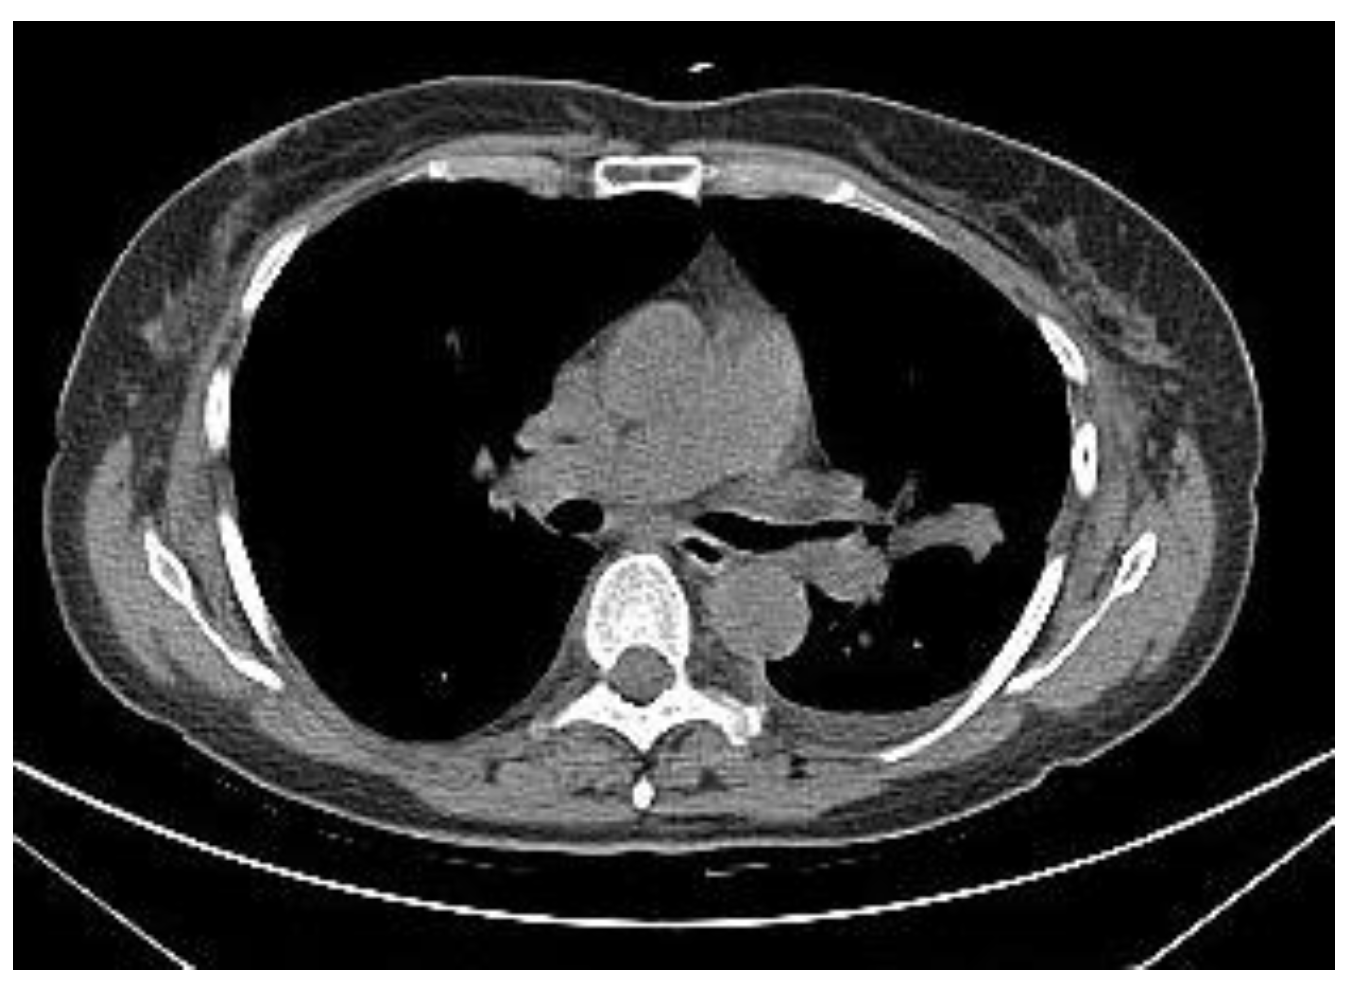

2.2.1. TIME 0: Lesion marking and SPECT Analysis